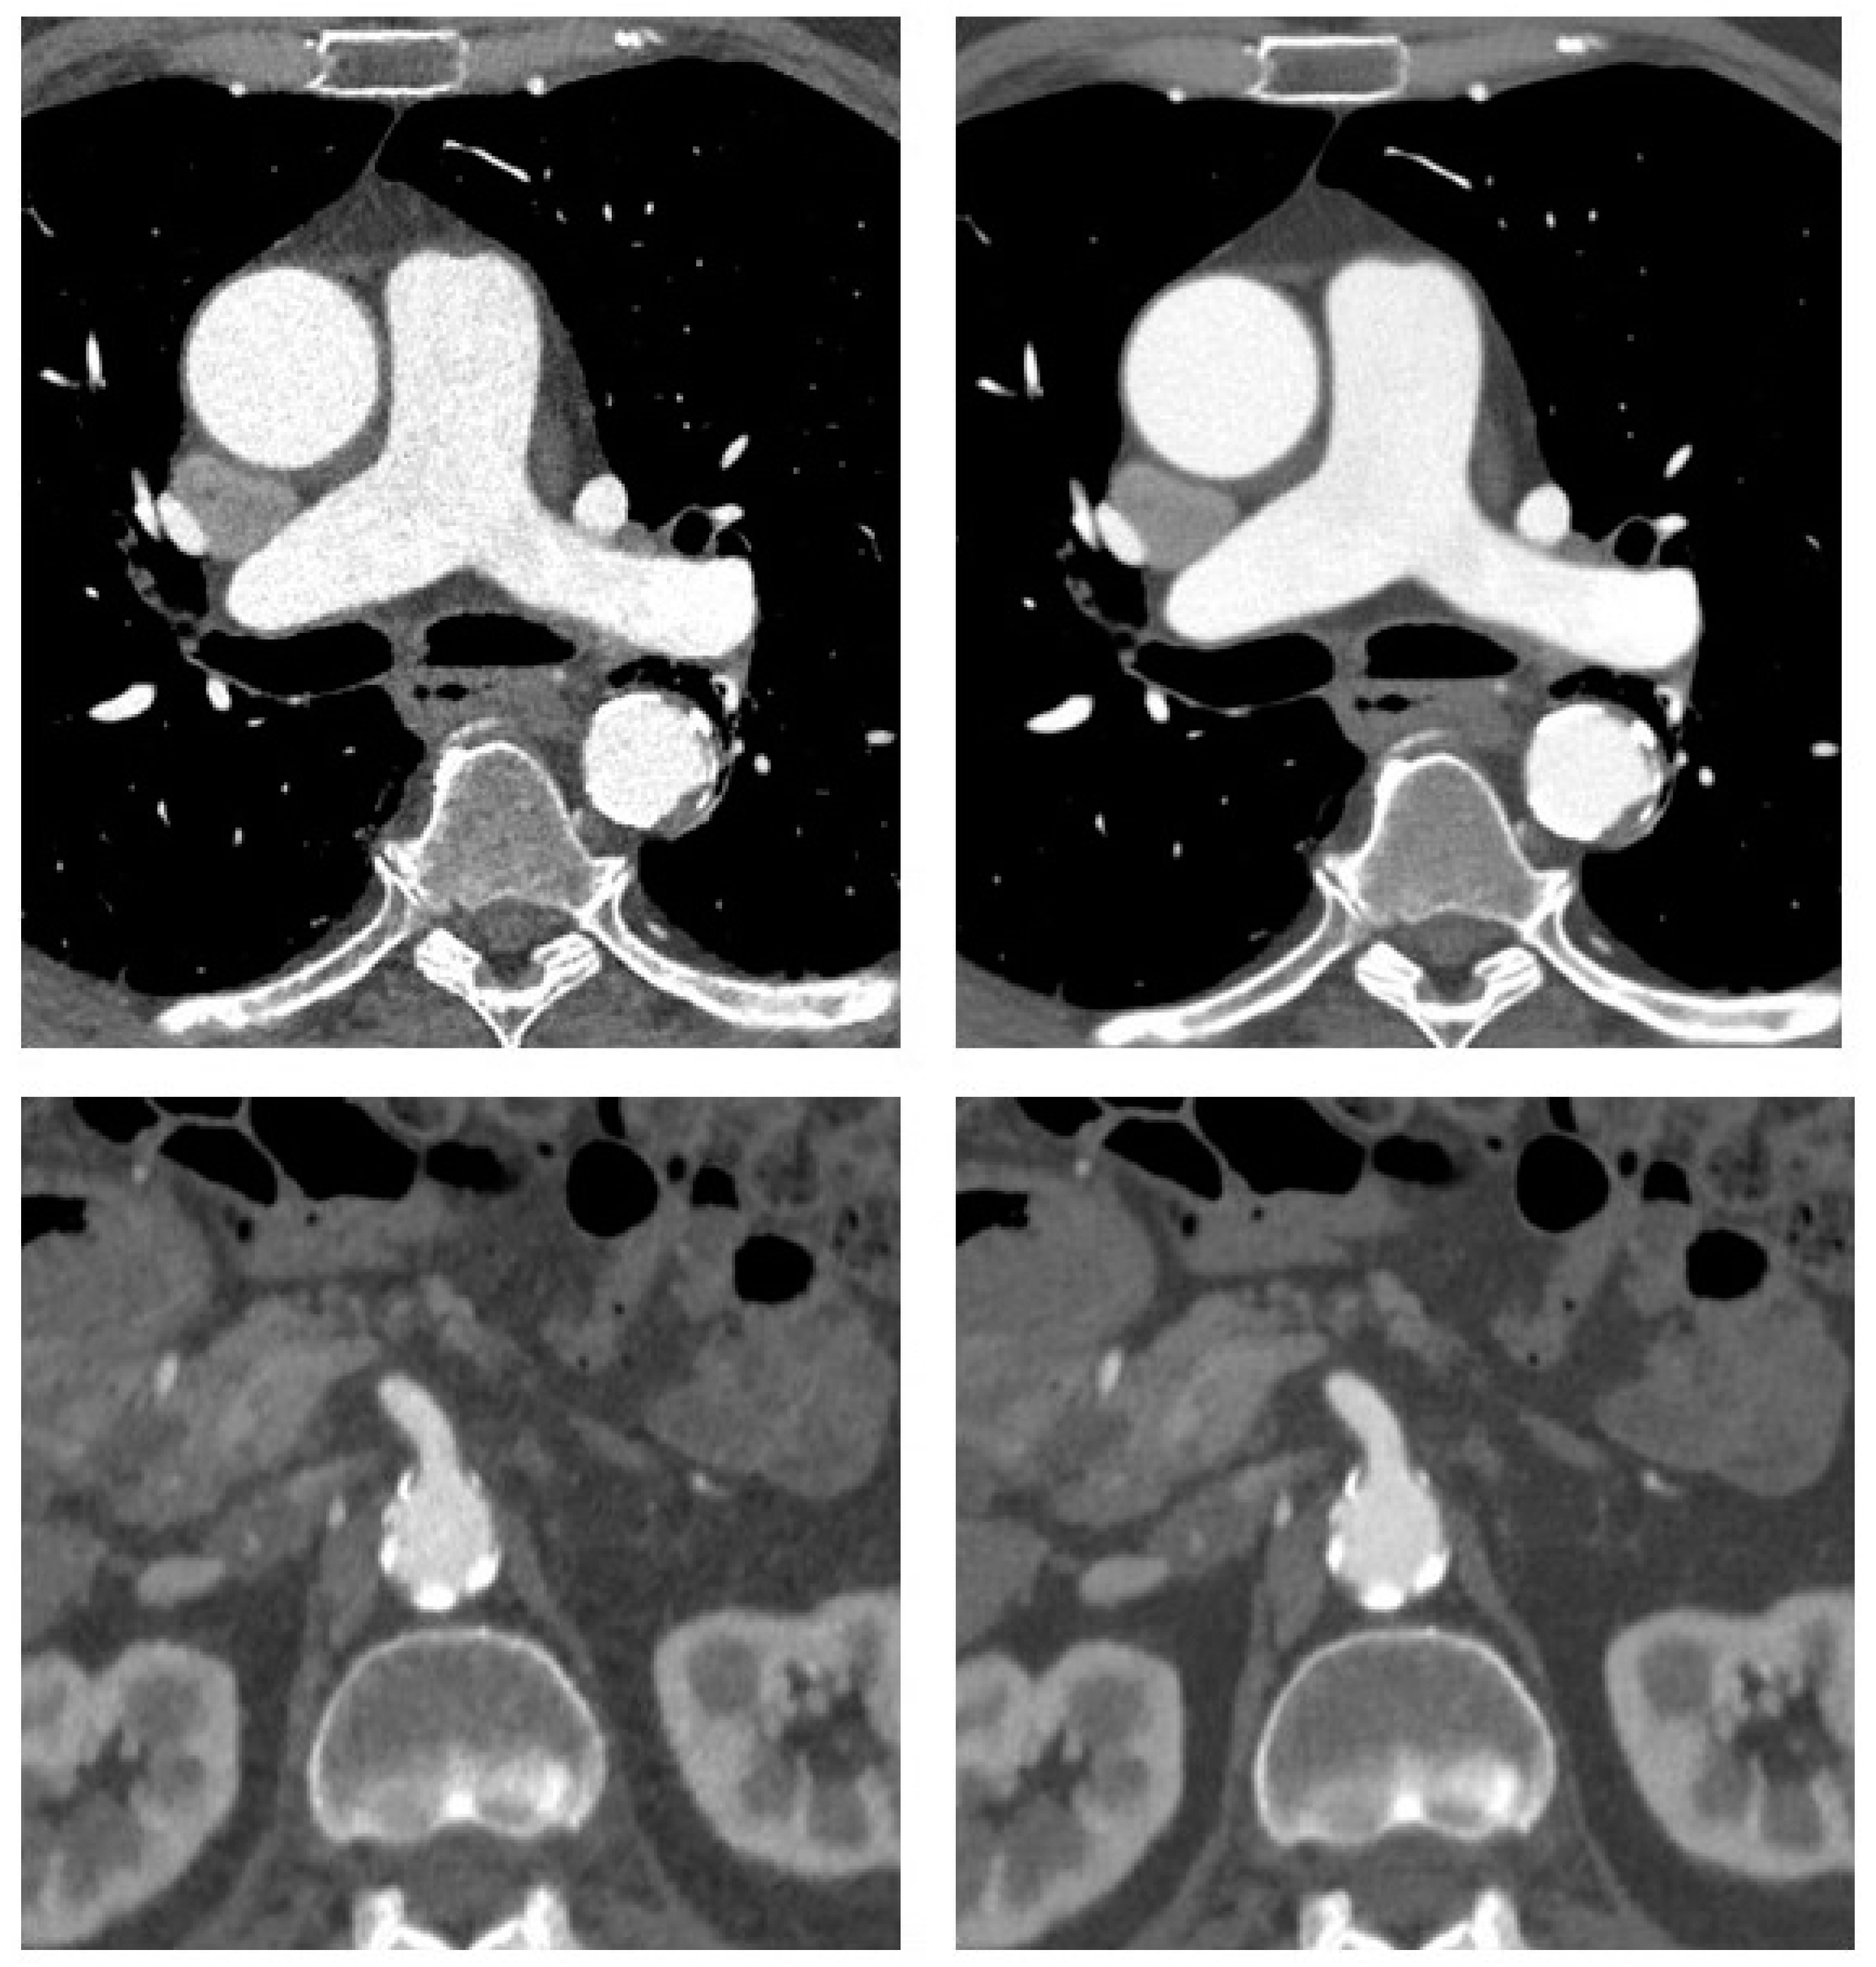

Figure 2.

CT angiography of the aorta in a 72-year-old man with coronary artery disease and suspected aneurysm of the ascending aorta. Transverse sections at the level of the ascending aorta and superior mesenteric artery origin are shown with adaptive statistical iterative reconstruction V (ASIR-V 60%, left) and deep-learning-based reconstruction (DLIR-H, right). There is mild aneurysmatic dilatation of the ascending aorta with a maximum diameter of 4.3 cm. Some atherosclerotic plaque along the descending aorta is also noted.